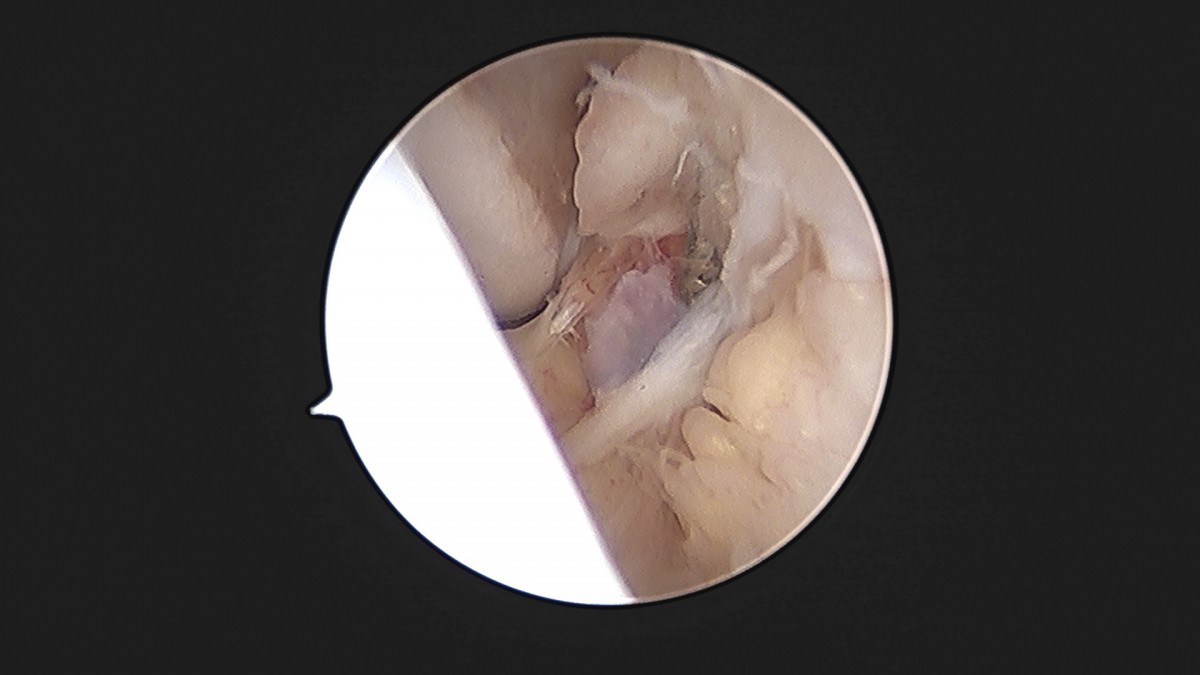

이재상원장님 발목 인대 봉합술 이주O 환자

dae765e4d9ac96aee867c9d6292d8784_1758007208_9216.jpg